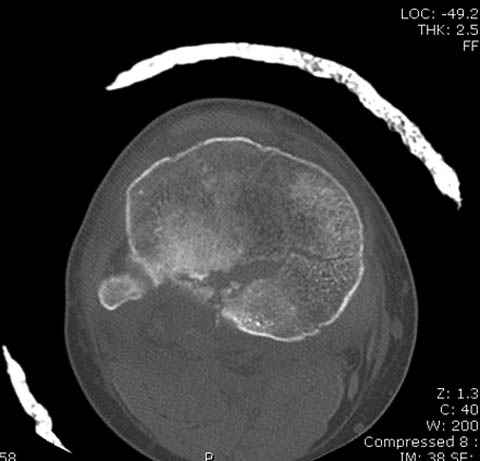

Пациенту сделали КТ - ухитрились сделать на шине Белера (не давал положить прямую ногу) - срезали передний отдел. Планируется на пятницу (24.12) на операцию - синтез длинной мыщелковой LCP-пластиной Synthes :). Отек ближе к слову умеренный (окружность голени +4 см по сравнению со здоровой). КТ и снимок на вытяжении прилагаются.

На представленных предоперационных срезах КТ огромный задне-медиальный фрагмент расположен больше кзади, чем медиально. Для планирования, кроме поперечных срезов, надо ориентироваться на корональные срезы, которые укажут топографию верхушки медиального фрагмента.

При сложных переломах тибиал плато для своего рода Damage Control мы иногда применяем поэтапную тактику. Сперва оперируется одна сторона, а потом после рекондиции мягких тканей окончательный этап.